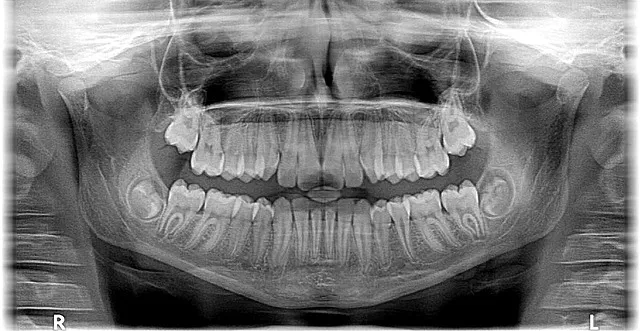

McCallen orthodontistry is a specialized branch of dentistry that focuses on correcting dental and facial misalignments, often referred to as malocclusion. It involves the use of various orthodontic appliances, such as braces, clear aligner trays, and other devices, to gradually adjust the position of teeth and jaws. The term ‘McCallen’ originates from Dr. John McCallen, a pioneering orthodontist who contributed significantly to the development of modern orthodontic techniques.

Orthodontics has a rich history dating back centuries. Ancient civilizations like the Greeks and Romans practiced basic tooth straightening techniques. However, it was in the 19th century that significant advancements began, with the introduction of fixed orthodontic appliances by Dr. Edward Angle in 1879. Modern orthodontics evolved over time, incorporating new materials, technologies, and treatment methods, culminating in the innovative practices we associate with McCallen orthodontistry today.

A 16-year-old patient presented with severe dental misalignment and low self-esteem due to her smile. Through a combination of Invisalign and patient education, the orthodontist successfully straightened her teeth within 18 months. This case highlights the effectiveness of invisible aligner treatments in addressing both cosmetic and functional concerns.

Case Study 2: Early Intervention for a Growing Child (Australia)

A young child with rapid jaw growth was identified as having a potential bite problem. The orthodontist implemented functional orthodesis, guiding proper jaw development. This proactive approach prevented future complications and ensured optimal oral health.